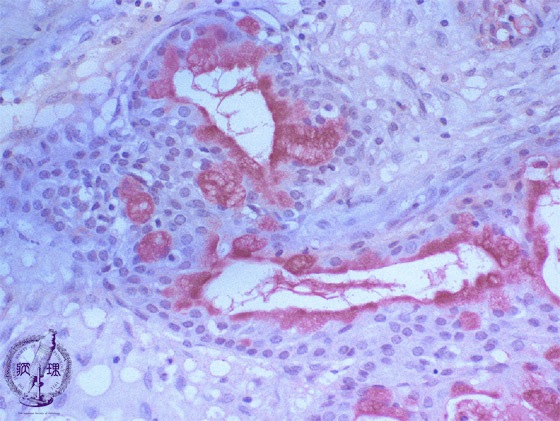

Microscopic finding (Mucicarmine stain, high-power view):Mucus producing cells and lumenal contents are stained red by mucicarmine stain (stain for epithelial mucin).

Click the image to see the enlarged image.

• There is no guidance by arrows.